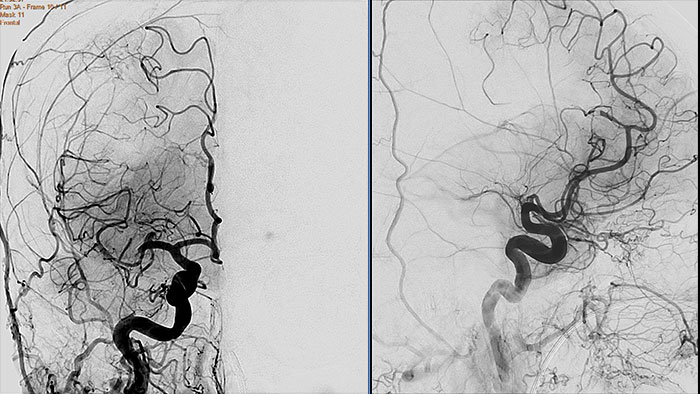

Vascular Processing - DSA (in MMV)

XA Vascular Processing - DSA (in MMV)

Contrast arterial structures with surrounding bone and soft tissue to assist in identification of vascular abnormalities

The XA Vascular Processing – DSA (in MMV) expands your workflow by allowing you to read and post-process iXR images virtually anywhere. Obtain images of arteries in various parts of the body using tools to perform standard and run subtractions, pixel shifting, and landmarking. This application also provides post-processing tools to edit and optimize the DSA XA data created in the interventional room.

Benefits

• Single image and ‘Run’ subtraction.

• Pixel Shifting to correct for patient movement during contrast injection and can be performed manually.

• Landmarking helps set a partial subtraction factor.

• Partial subtracted image shows (to a certain degree) the complete image, with the contrast enhanced depending on the subtraction factor.

• Same workflow as in the Philips Allura system.

Viewing (in MMV)

XA Viewing (in MMV)

Comprehensive reviewing tool for multiple modalities, all in a single viewer

The Multi Modality Viewer (MMV) now supports viewing and post processing of angiography images and series. Review and perform analysis of angiographic imaging alongside other modalities for a comprehensive review of the patient case. Perform vascular processing of images (Digital Subtraction Angiography) – subtraction, pixel shifting and land marking. Include key images into the generic MMV report. Prior to the intervention, relevant diagnostic (MR and or CT) data can be bookmarked and automatically retrieved upon patient selection in the Allura, or the Azurion suites.

• Enable a comprehensive review of a patient case across all modalities –  CT/MR/NM/US/Angio – in a single environment.

• Advance viewing and post-processing (DSA) of angiographic images and series.

• Annotate and perform basic measurements on images (provided the image is pre-calibrated).

• Automatic retrieval of relevant diagnostic (CT and/or MR) data to support the intervention using iBookmark.

• Reporting also supported; key images can be send to an MMV generic report.